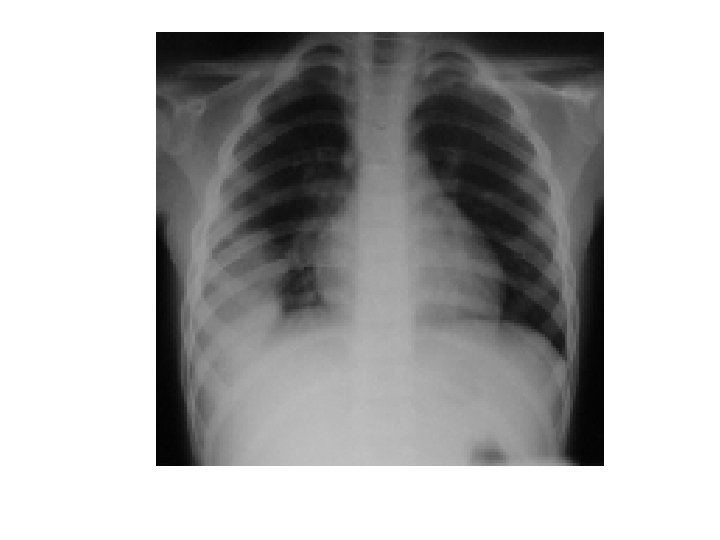

Pnömoni

Yapılması gerekenler • Öykü (standard+antibiyotik kullanımı, risk faktörleri) • Fizik muayene, vital bulgular (standard+ ağırlık faktörleri) • Temel Lab (CRP, kan sayımı, ALT, bilirubinler, kreatinin, Na, LDH) • Balgam incelemesi • Akciğer grafisi

Hastaneye yatırılma ölçütleri Radyolojik bulgular (akciğer grafisinde) 1 -Multilober tutulum 2 -Kavite 3 -Plevral efüzyon 4 -Hızlı progresyon

Tanı 1 -Akut ateş 2 -Yeni başlıyan öksürük, balgam ve/veya dispne 3 -Akciğer oskültasyon bulguları 4 -Akc grafisi (PA ve lateral) 5 -Lökosit sayısı ve kantitatif CRP 6 -Kaliteli balgamın Gram boyası ve kültürü